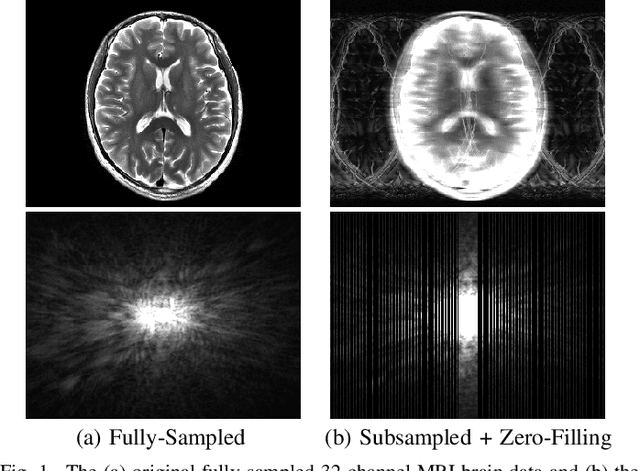

Abstract:We propose and evaluate a new MRI reconstruction method named LORAKI that trains an autocalibrated scan-specific recurrent neural network (RNN) to recover missing k-space data. Methods like GRAPPA, SPIRiT, and AC-LORAKS assume that k-space data has shift-invariant autoregressive structure, and that the scan-specific autoregression relationships needed to recover missing samples can be learned from fully-sampled autocalibration (ACS) data. Recently, the structure of the linear GRAPPA method has been translated into a nonlinear deep learning method named RAKI. RAKI uses ACS data to train an artificial neural network to interpolate missing k-space samples, and often outperforms GRAPPA. In this work, we apply a similar principle to translate the linear AC-LORAKS method (simultaneously incorporating support, phase, and parallel imaging constraints) into a nonlinear deep learning method named LORAKI. Since AC-LORAKS is iterative and convolutional, LORAKI takes the form of a convolutional RNN. This new architecture admits a wide range of sampling patterns, and even calibrationless patterns are possible if synthetic ACS data is generated. The performance of LORAKI was evaluated with retrospectively undersampled brain datasets, with comparisons against other related reconstruction methods. Results suggest that LORAKI can provide improved reconstruction compared to other scan-specific autocalibrated reconstruction methods like GRAPPA, RAKI, and AC-LORAKS. LORAKI offers a new deep-learning approach to MRI reconstruction based on RNNs in k-space, and enables improved image quality and enhanced sampling flexibility.